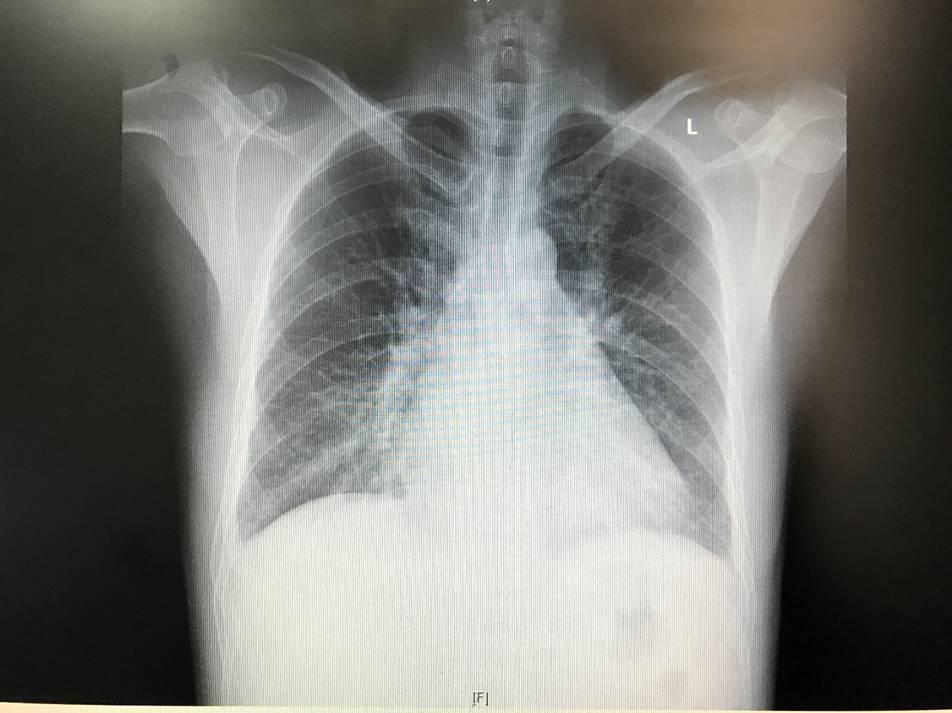

胸片